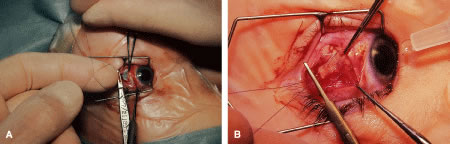

RESECTION PROCEDURE: LIMBAL APPROACH

Incision is made into the conjunctiva at the limbus (Fig. 64).

Fig. 64. After the stay sutures have been placed, the conjunctiva is tented with a forceps. An incision is made at the limbus.

The assistant elevates the conjunctiva while the surgeon uses a Stevens' hook to elevate the rectus muscle (Fig. 65). A Jameson muscle hook is passed under the muscle tendon in a plane that is tangential to the scleral surface, about 3 mm behind the tented rectus muscle insertion. Figure 66 shows the rectus muscle on the Jameson hook.

Fig. 65. The rectus muscle insertion is secured with a Jameson hook by passing the hook tangential to the globe.

Fig. 66. The conjunctiva is held up with a forceps while the surgeon holds the rectus muscle tissue on the Jameson hook. The tip of the hook is exposed and is covered by intermuscular septa and anterior Tenon's capsule.

The surgeon cuts the intermuscular septa free from the muscle capsule (Fig. 67). A Castroviejo caliper is used to measure the amount of tendon that will be resected (Fig. 68). A Jameson resection clamp is placed on the muscle at the point of anticipated resection. Measurement is made from the portion of tendon that is on the posterior edge of the Jameson hook to the resection clamp. Exposure is facilitated with a Desmarres retractor.

Fig. 67. The intermuscular septa are cut with a Westcott scissors.

Fig. 68. A Jameson resection clamp is applied to the muscle tendon. A caliper is used to measure the amount of tendon that will be resected.

The muscle is cut free from its insertion (Fig. 69). The surgeon holds the Jameson clamp to elevate the muscle from the globe, and, using the other hand, the surgeon cuts the muscle free from the globe. The muscle stump is cut so that it is flush with the globe.

Fig. 69. A Desmarres retractor is used to provide improved exposure. A Westcott scissors is used to cut the muscle free from its insertion.

The globe is stabilized with a 0.5-mm-toothed Castroviejo forceps (Figs. 70 and 71). A mattress stitch with a double-armed 6-0 synthetic absorbable suture is placed through the most inferior portion of the insertion. The second needle is passed 1 mm below the central portion of the insertion. The initial penetration of the needle is just anterior to the insertion, and a secure bite is taken of the former insertion so that the needle exits just posterior to the old insertion. The needle is then passed underneath the Jameson resection clamp through muscle tendon, and the two sutures are held with a bulldog clamp to keep them separate from the sutures that are later passed through the upper pole of the insertion. Figure 71 shows the sutures being tied. This maneuver will effectively bring the resected muscle tendon up so that it can be reinserted at the insertion. Once the muscle is tied securely, the Jameson resection clamp is released and then advanced to the cut end of the insertion (Fig. 72). Under direct visualization, a Westcott scissors is used to trim the excess muscle stump. Care is taken to leave at least 1 mm of muscle tendon in front of the two sutures that secure the muscle to the insertion. After the muscle stump has been inspected, the conjunctiva is advanced back to the limbus (Fig. 73). Two 8-0 collagen sutures are used to secure the conjunctiva at the limbus. The small open radial portion of the incision will heal without suture closure. If the surgeon “buries the knots” under the conjunctiva near the limbus, the patient will have less foreign body sensation. Figure 74 shows the eye immediately after a recess-resect procedure. The conjunctiva should be smooth at the limbus to prevent disruption of the tear layer and formation of dellen. The eye is not patched. Antibiotic drops or antibiotic-steroid drops may be used at the discretion of the surgeon.

Fig. 70. A double-armed mattress suture is passed through the anterior portion of the insertion, exiting posterior to the severed stump of the insertion. The two needles are passed back through the muscle tendon just posterior to the Jameson clamp.

Fig. 71. Knots are tied to secure the resected muscle at its new insertion. The Jameson resection clamp has already been moved anteriorly on muscle before tying the sutures.

Fig. 72. The Jameson clamp is removed and reinserted closer to the cut portion of tendon, near the old insertion. The muscle is then resected.

Fig. 73. The conjunctiva is closed with two interrupted 8-0 collagen sutures.

Fig. 74. The immediate postoperative appearance of an eye that has had a recess-resect procedure with a limbal approach.